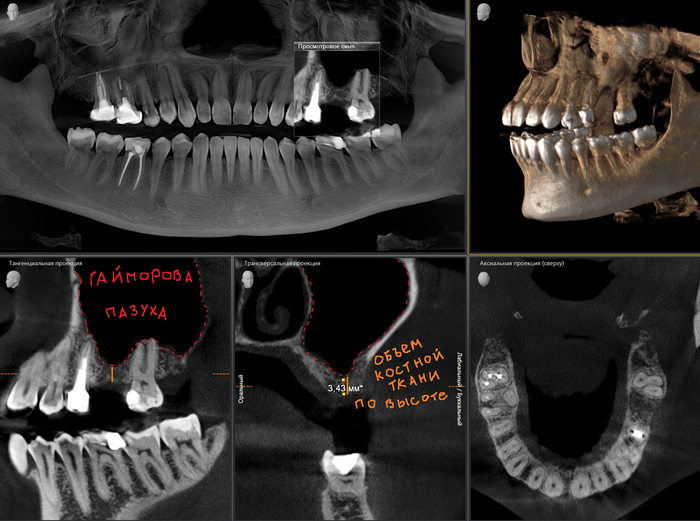

А теперь пример синус-лифтинга и имплантации, но через 2 месяца после того, как был удален 6-ой зуб на верхней челюсти. Этой пациентке удалили 6-ку около недели назад в другой клинике. Ассистентка сделала компьютерную томографию.

В связи с тем, что после удаления прошла всего неделя, то и на снимке мы видим «темную дыру», как ту, что оставила в твоем сердце бывшая. В том месте, где раньше был зуб. То есть костной ткани в этой области нет. К операции я приступил через 2 месяца. Повторную компьютерную томографию после заживления лунки делать не стали, но поверьте все зажило достаточно для того, чтобы можно было провести операцию. В ходе операции жесткой стабилизации имплантата добиться не удалось, поэтому я принял решение установить заглушку, а не формирователь десны. Почему? А потому, что если пациентка начнет грызть сухари, то на имплантат, в частности формирователь, может быть оказано сильное давление, в связи с чем имплантат может расшататься или «улететь» в пазуху. Заодно в утиль пошла и 8-ка.

Как мы видим условия в данном случае несколько хуже около 2мм. Но это не помешало нам провести операцию в полном объеме.